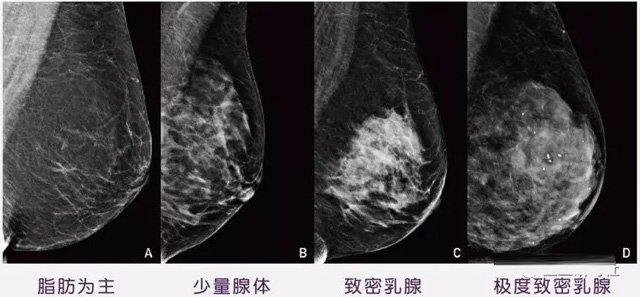

女性乳腺的自我检查,特别是注意有小结节,肿块,乳头有液体渗出情况,需要通过乳腺DR,X光线,磁共振等影像技术检查。胸的大小跟乳腺癌没多大关系,乳腺的密度大发病率高一些,胸小脂肪少致密性大。更容易乳腺癌。这个还不能通过自我检查来确认。致密乳腺组织看上去是白色或浅灰色需要通过乳腺X射线检查。